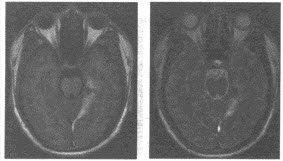

患者,男,56岁。因背部疼痛2个月入院;查体:胸椎T~T棘突和椎旁有压痛,胸椎活动受限。体温38.4℃,X线平片和CT见下图。

(单选题)首先考虑为何种疾病()